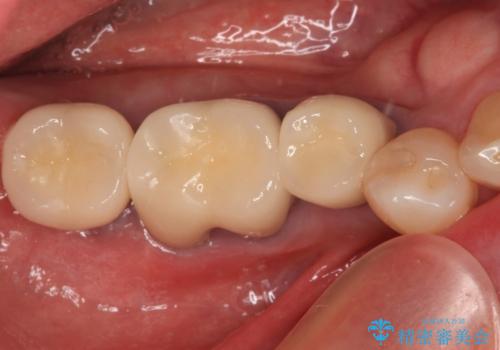

クラウンがすぐに外れてしまう 歯冠長延長術を用いた補綴治療

歯の高さが低く、かぶせものを安定して維持させることができないため、歯冠長延長術により歯の高さを増大させた上で、オールセラミッククラウンにて補綴することとしました。

歯の高さが増したことで、かぶせものが外れにくくなったことはもちろん、今まで無理と言われていたセラミッククラウンも装着でき、さらには歯間部の清掃性も向上したため、患者様には大変満足していただけました。